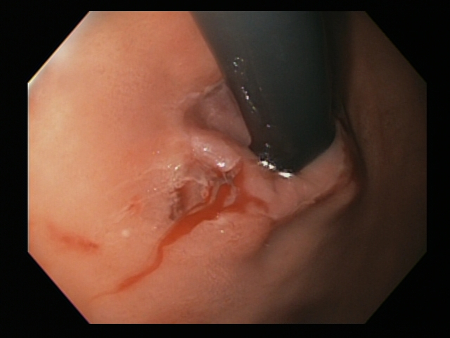

Laceração de Mallory-Weiss

Laceração de Mallory Weiss com sangramento observada em retroflexão

Do acervo pessoal de Douglas Adler; usado com permissão